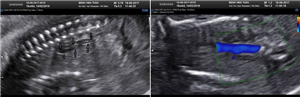

CLS: Siêu âm tim thai thông liên thất